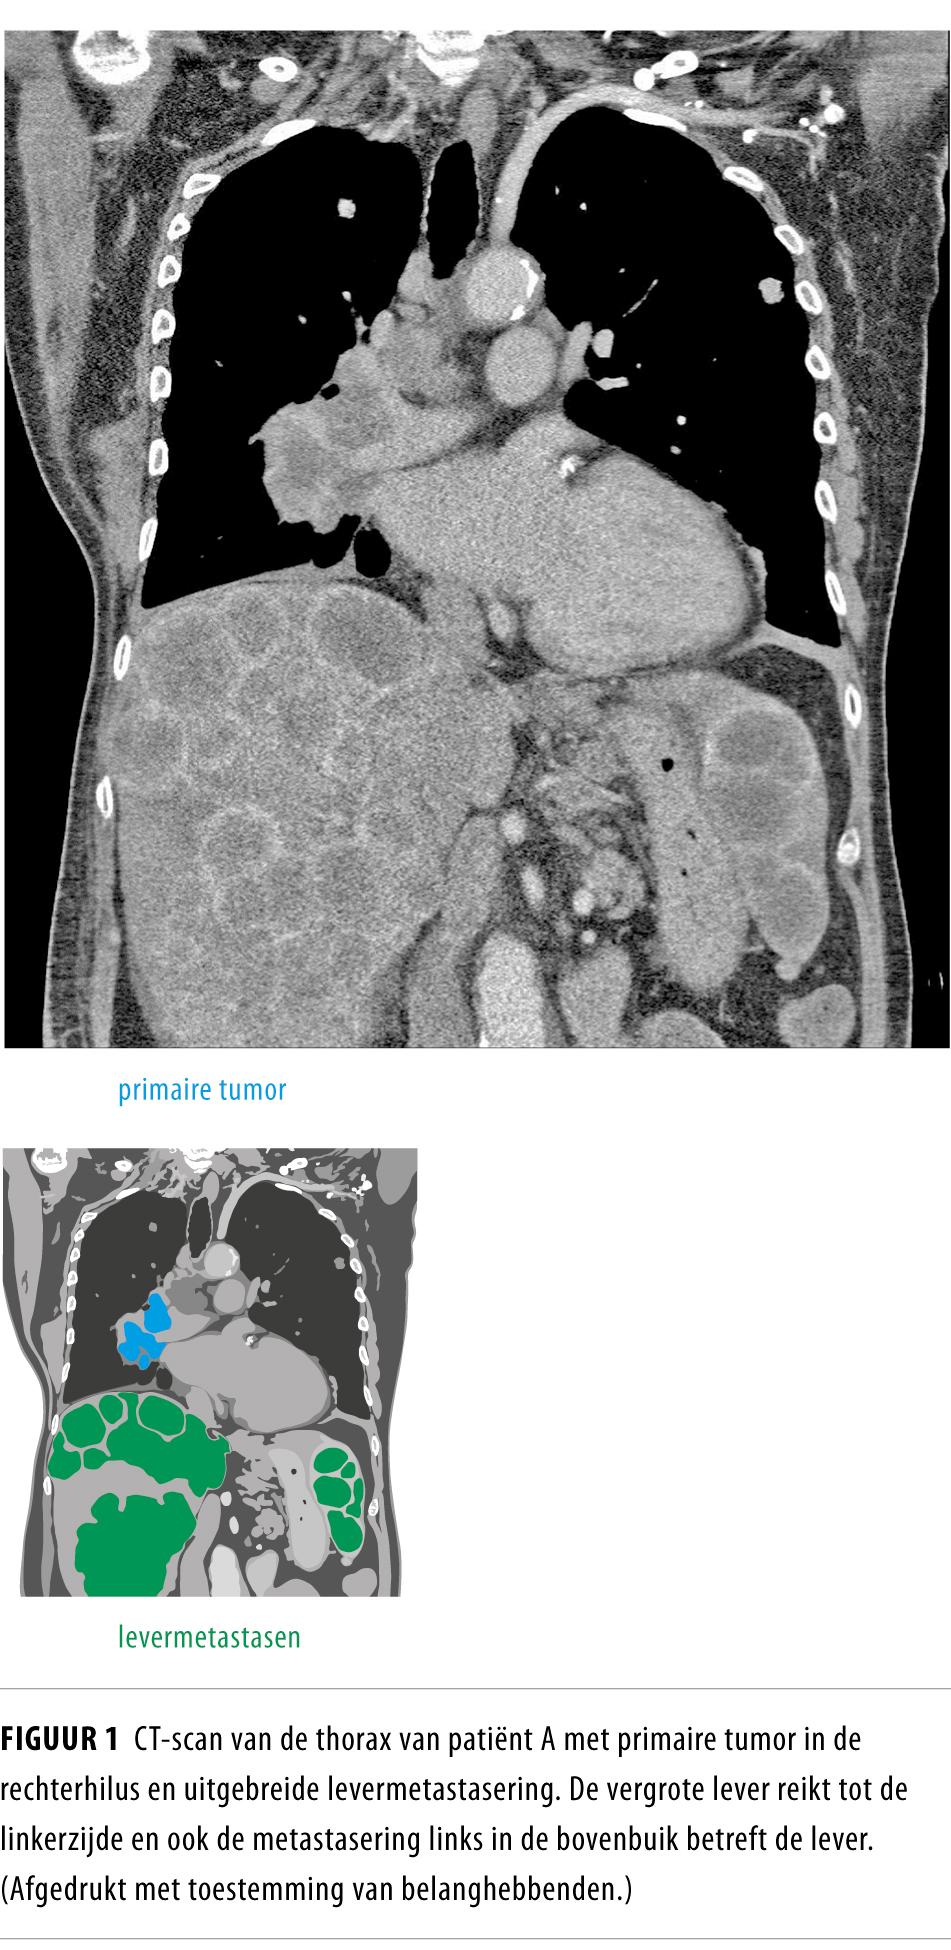

Tumorlysissyndroom bij kleincellig longcarcinoom NTvG